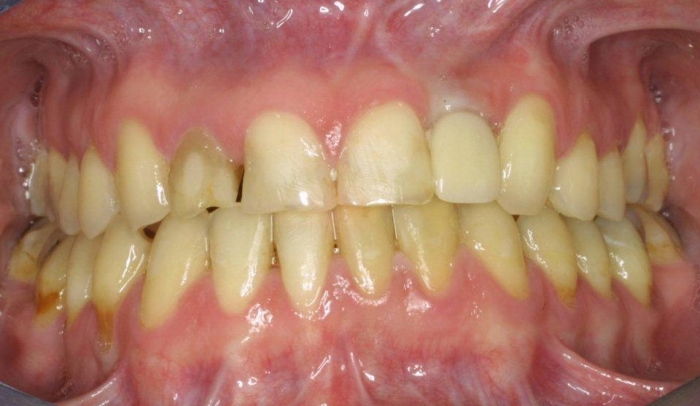

Sorriso inicial